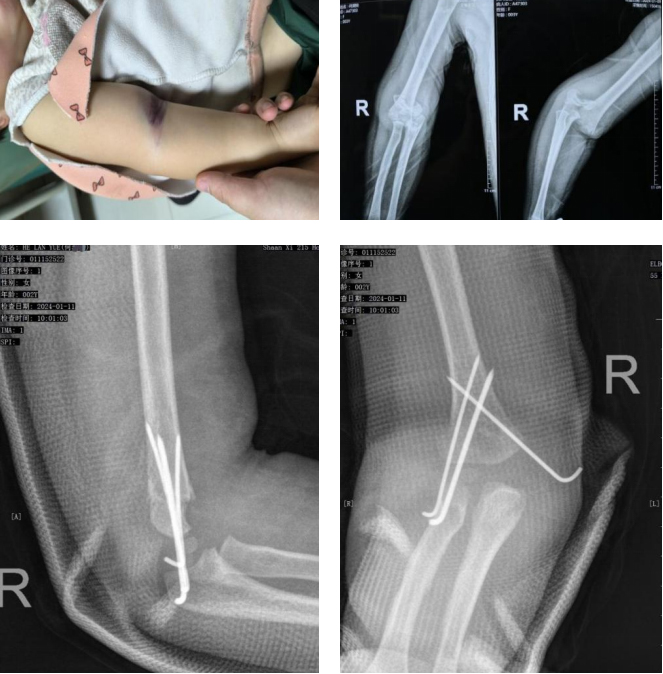

随着微创、麻醉、监护等技术的进步,近日,二一五医院骨科医院小儿骨科·创伤骨科正式开展日间手术,为患者带来了更优质、更便捷的就医体验。从入院、手术、术后恢复仅需24小时。 1月9日下午2点左右,家住乾县,何先生...